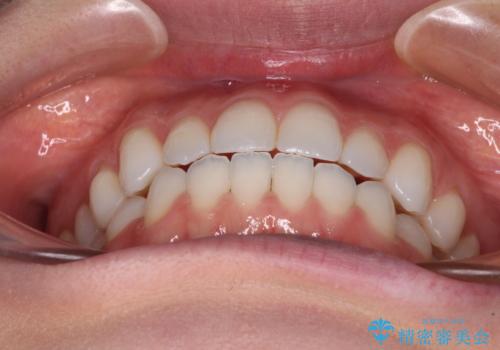

上下前歯が接触しない オープンバイトをインビザラインで改善

- 前歯の上下スペースによる食べにくさを気にして来院された患者様です。

インビザラインにより上下の前歯の隙間を閉じていくこととしました。

上下の奥歯を圧下させるようにすることで、前歯を接触させるように計画しました。

上下の隙間に舌が入り込むことがオープンバイトの原因であったため、舌の筋肉のトレーニングも並行して行い、後戻りの抑制を図りました。